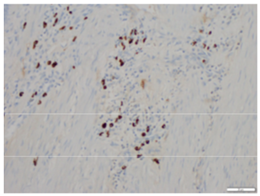

The entire strictured area was submitted for microscopic analysis. These sections showed chronic inflammation, crypt architectural distortion, and marked submucosal fibrosis with a multifocal lymphoplasmacytic infiltrate (Figure 1 & 2). No neoplasm was identified. Immunohistochemical stains for IgG (Figure 3) and IgG4 (Figure 4) were performed that highlighted foci of lymphoplasmacytic aggregates and many IgG4 positive plasma cells within the fibrotic areas. The histologic and immunophenotypic evidence supported the diagnosis of IgG4 related enteropathy in this patient.

Figure 3 Immunohistochemical stains for IgG.

Figure 4 Immunohistochemical stains for IgG4.